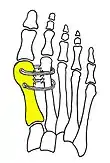

- For recurrence correction after osteotomy procedure (Fig. 8)

Late deformity recurrence can happen after osteotomy (bone-breaking) procedures because osteotomy surgeries do not specifically stabilize first metatarsal bone.